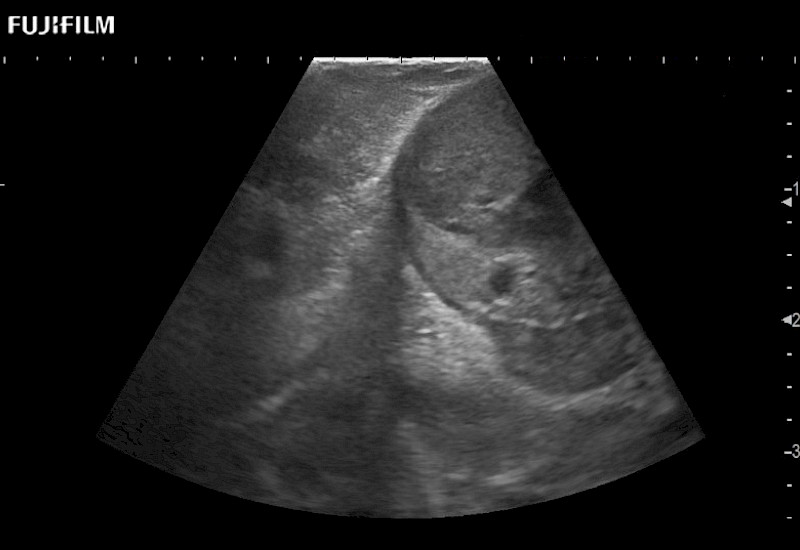

Exclusive linear array robotic surgery transducer.

Features:

Main Specifications: